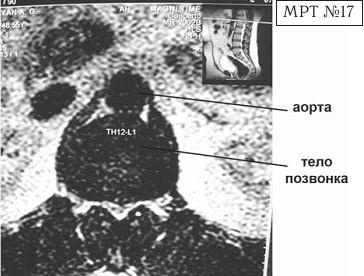

Вентральная локализация грыжи межпозвонкового диска как правило клинически ничем характерным не проявляется и определяется случайно (при обследованиях, связанных с другими заболеваниями позвоночника). Однако она не менее опасна, чем дорсальная грыжа межпозвонкового диска, особенно из-за близкого расположения аорты. Дело в том, что по анатомическому расположению брюшная часть аорты начинается на уровне XII грудного позвонка и, проходя по передней поверхности тел поясничных позвонков (немного левее срединной линии), продолжается практически до уровня середины тела IV поясничного позвонка. При вентральной грыже межпозвонкового диска значительных размеров в верхних сегментах поясничного отдела позвоночника могут возникать «конфликты» грыжи с аортой и соответственно спаечные процессы с вовлечением в них последней, что в свою очередь может привести к нарушению кровообращения в области малого таза и нижних конечностей.

На МРТ № 17 наблюдается вентральная грыжа межпозвонкового диска в сегменте ThXII-LI с выраженными спаечными процессами на этом уровне, с вовлечением в данный процесс брюшной аорты